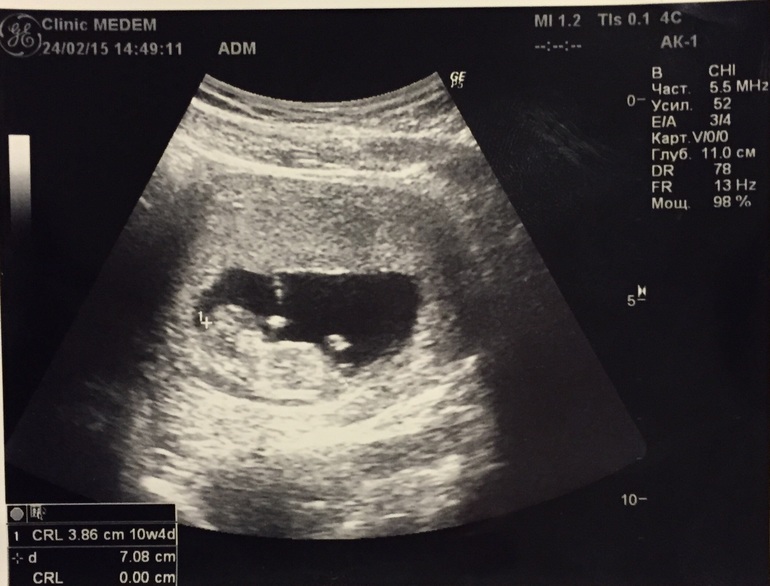

Бывший опарыш уже человечище! С характером, весь в отца. Спал как сурок, жопой к нам и ни за что рожу не показал. Люблю его:)))))

10 недель и 4 дня по УЗИ. Первое УЗИ по животу! Праздник празднииик! Дождались!

Фото на паспорт!

Лапы смешные шопипец)) йожык в тумане едрить:)))))